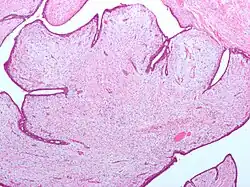

| Fibroepithelial neoplasm (Phyllodes tumor). | |

- Phyllodes tumor of the breast